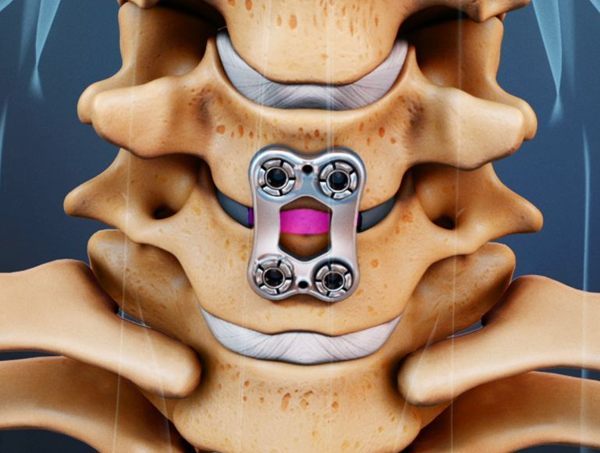

Artificial Disc Replacement

Replaces the damaged disc with an artificial one to maintain motion.